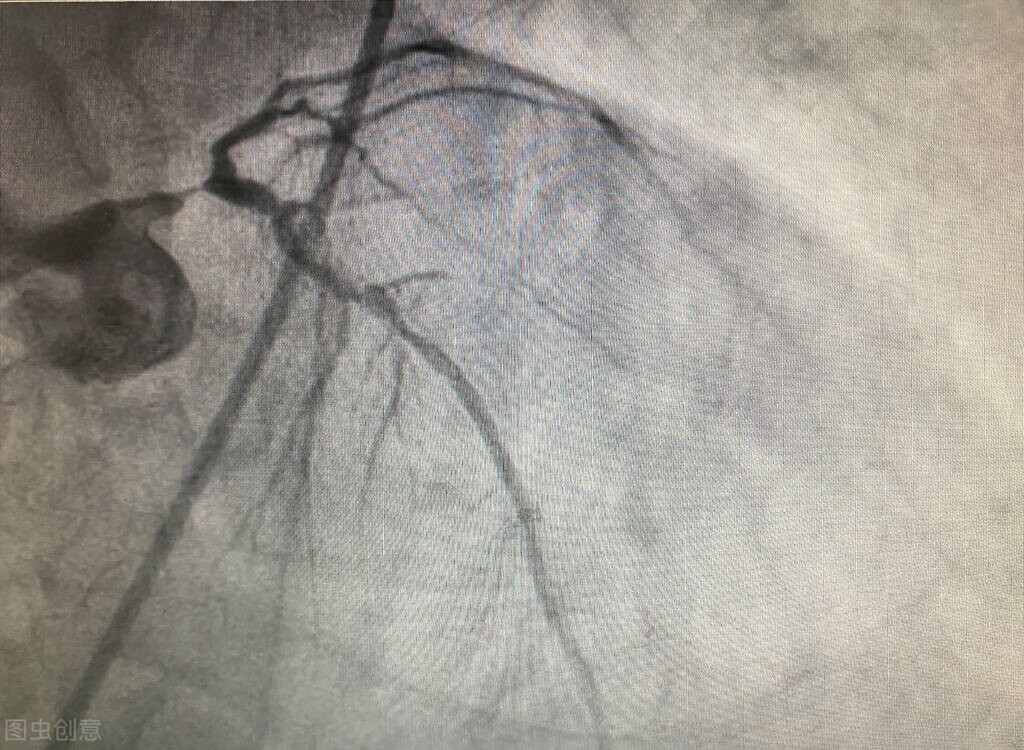

随后医生为毛大叔进行了详细地检查,结果发现毛大叔的心脏射血功能指数已经降到了35%,正常的心脏射血分数应该在50%以上!急诊冠脉造影发现,心脏冠脉血管前降支动脉狭窄85%,远端狭窄75%,左回旋支远端狭窄95%,左室后降支狭窄80%!

并且,在冠脉血管中可见不同数量大小的斑块!

冠心病造影